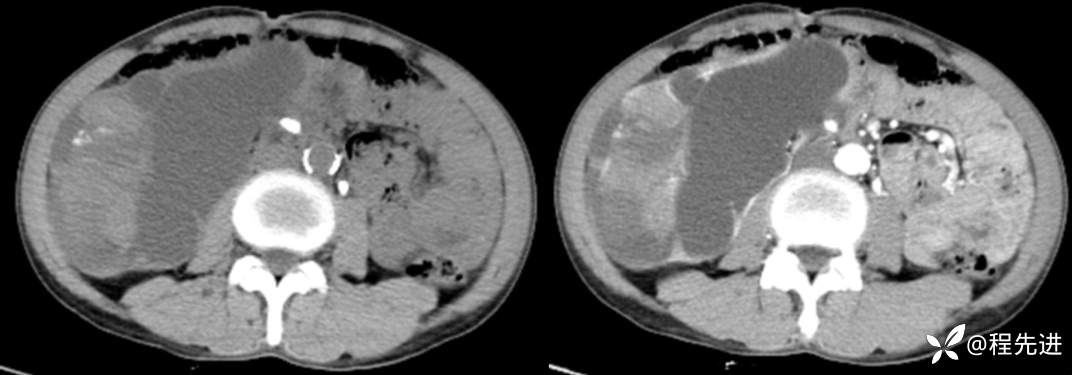

来张特定(左平扫,中动脉期,右静脉期)